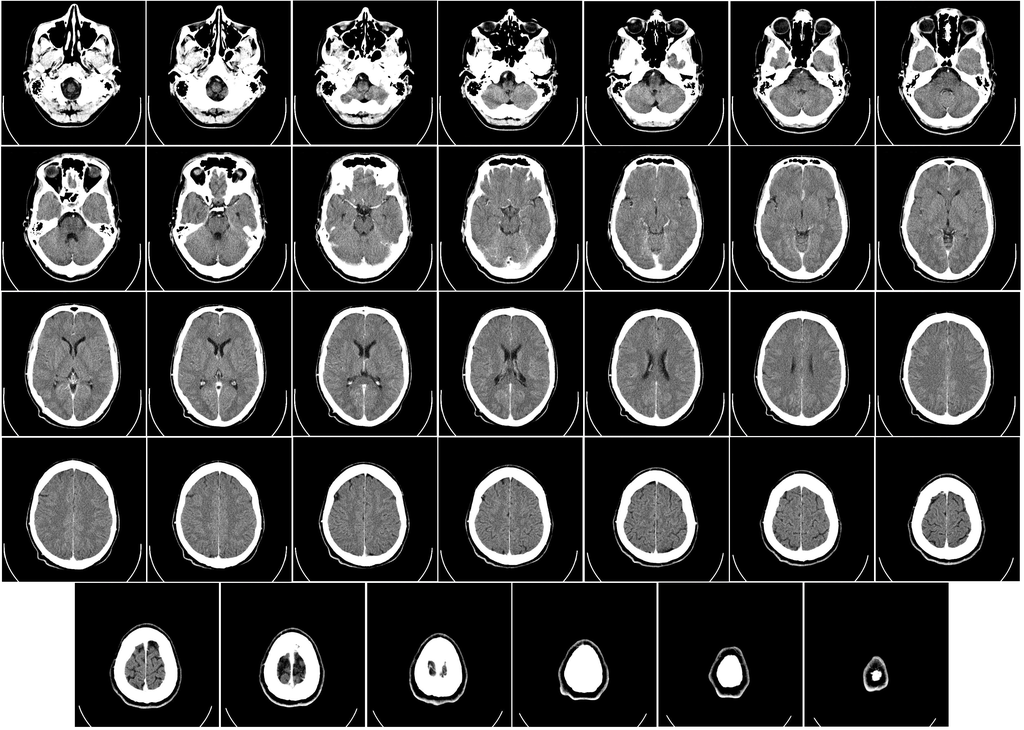

Perhaps the most important development came in the 1970s, with the first X-ray computed tomography machine, or CT scan. Using sensors to detect the output of X-rays beamed through the patient’s body, the machine creates elaborate images of bones, organs, and soft tissue all at once. Because each substance in the body is penetrated by the beam to a different degree, the machine can successfully distinguish between an arm and a spleen, and carefully recreate an impression of both. “That’s the most modern application of X-ray technology,” Banerjee says.

Tube current modulation, in the context of a CT scan, means the dose of the radiation is varied according to the part of the body under review. In a full-body scan, more radiation will be sent to the rock-hard skull than the airy lungs, according to Allen, thereby managing overall exposure to the beams. Iterative reconstruction, meanwhile, is the process by which an algorithm in the CT scanner pieces together high-quality images of the body. By reducing noise and clearing up the image, patients can spend less time in the donut-shaped CT machine, being bombarded with X-rays and resulting radiation.

The process of producing a medical radiograph looks much the same as it did when the X-ray was first discovered. X-rays are generated, and the resulting beams are pointed at a human target; the images created from this process are analyzed by other humans. But what about the X-rays of the future?